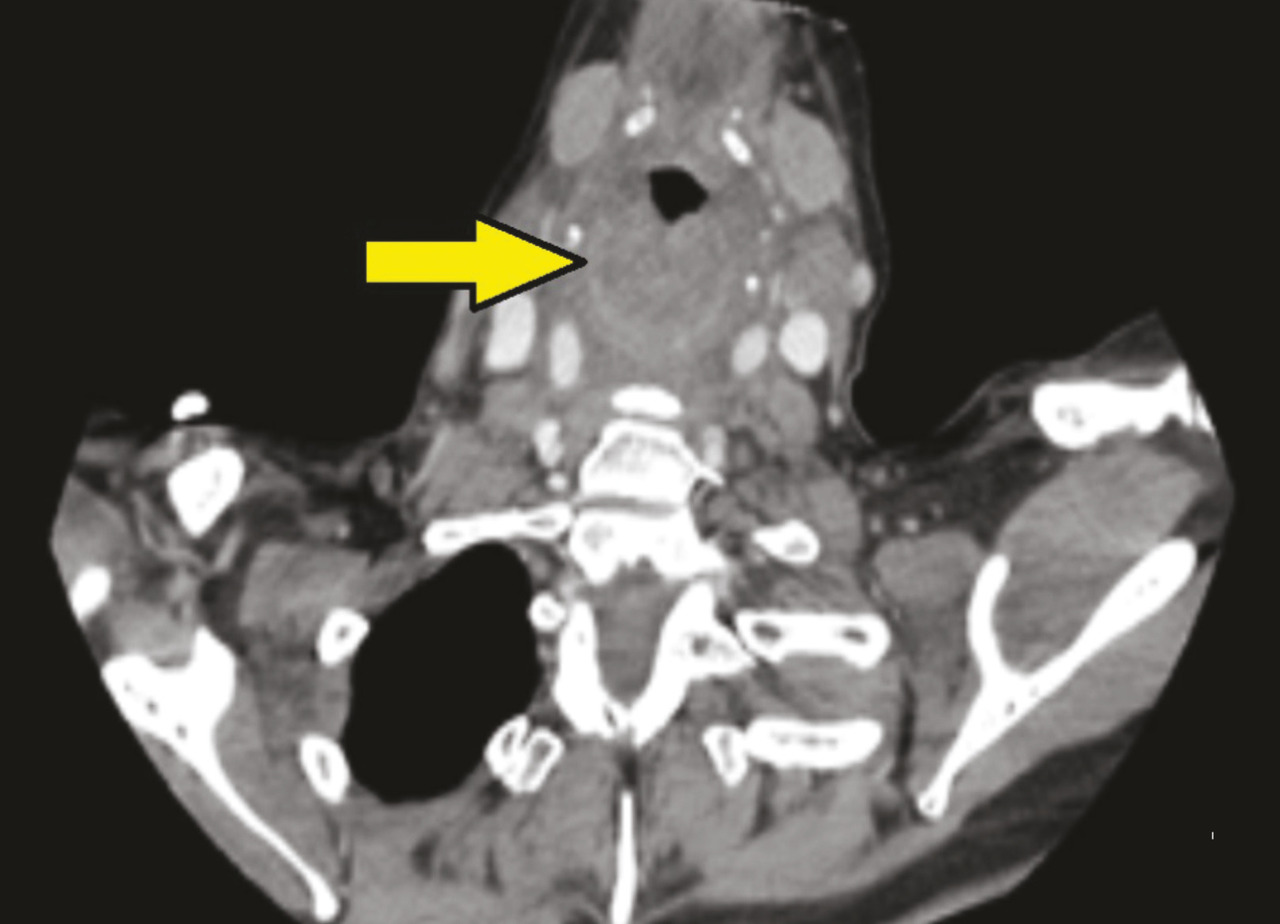

Une patiente de 56 ans se présente aux urgences avec un tableau fébrile à 39 °C évoluant depuis vingt-quatre heures, associant odynophagie et dyspnée. Elle est polypnéique à 25 cycles/min et désature à 89 %. Elle est assise, bouche ouverte avec une hypersialorrhée, dysphonique. La palpation cervicale est douloureuse, sans cellulite ni emphysème. L’ORL se déplace rapidement pour réaliser une nasofibroscopie, qui confirme le diagnostic d’épiglottite non abcédée. À sa demande, un scanner cervical injecté est réalisé sans allonger la patiente. Il retrouve un épaississement pariétal circonférentiel sténosant de la paroi laryngée responsable d’une réduction du calibre de la lumière laryngée d’environ 70 % (fig. 1 et 2 ).